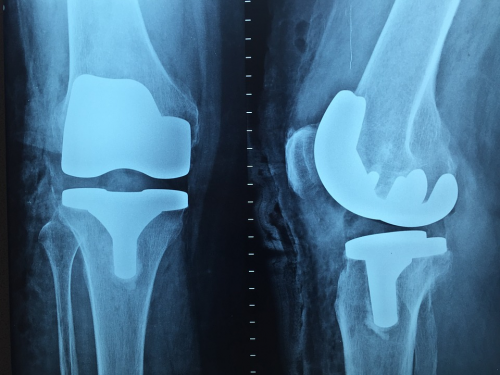

如果软骨组织磨蚀程度严重,患者可能需要接受关节镜、矫正内翻或人工关节置换手术。[关节镜是针对因碎骨而影响关节活动能力的患者,至于矫正内翻则需要将胫骨切开再植入钢片,一般是针对较年轻的患者。至于最常见的人工关节置换手术至今已有40年历史,手术是将原本的关节取走,再置入股骨及胫骨假体及人工关节。本港大约于7年前采用计算机导航提升准确度,今年更引入了机械臂手术,能于手术前以计算机扫描了解关节及骨骼的结构,令手术精准度更高。]

半膝关节置换术可保留十字韧带

除了全膝关节置换术,若患者仍有部分关节完好,张医生建议可考虑进行半膝关节置换手术。[置换半膝保留部分关节及其中央部分的十字韧带,好处是创伤及出血较少,而且伤口大小亦有明显差别,复康时间更快。而且保留十字韧带能帮助人体感受关节活动,故患者感觉会较为自然。这种手术在香港已有超过15年历史,我们最近检视这些病人的临床表现,发现只有少数个案需要进行翻修,数字比预算中低,故适合半膝关节置换手术的患者毋须太担心原本保留的关节会出现退化问题。]